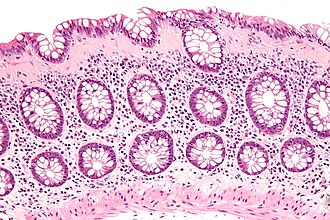

Collagenous colitis. H&E stain.

LM intraepithelial lymphocytes (>20/100 enterocytes), subepithelial collagen band (>= 10 micrometres thick)

• Intraepithelial lymphocytes - important.

• Collagenous material in the lamina propria (pink on H&E) -- key feature.

• Can be demonstrated with a trichrome stain -- collagen = green on trichrome.

• Subepithelial collagen needs to be >= 10 micrometres thick for diagnosis.[4]

• 8 micrometres is the diameter of a RBC.

• The normal thickness of the subepithelial collagen is 3 micrometres.[4]

• Transverse colon usually thickest - in one series ~ 47 micrometres on average.[5]

• Thickening is usually patchy.[6]

• Thickening "follows the crypts from the surface" - useful for differentiating from tangential sections of the basement membrane.[7]

• Collagen may envelope capillaries - useful to discern from basement membrane.[7]

The sections show colonic mucosa with abundant intraepithelial lymphocytes (>20 lymphocytes/100 surface epithelial cells). A prominent collagen band is apparent below the epithelium (>10 micrometres thick). The glandular architecture is within normal limits.

There are no granulomas. No neutrophilic cryptitis is apparent. The epithelium matures appropriately to the surface.